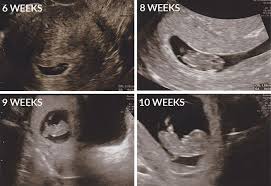

When you re 6 0 weeks pregnant your baby s hearts should be beating and the sonographer should be able to detect them at this point.

Through vaginal ultrasound the sound waves are very likely produce a clearer image at this stage. An ultrasound scan at 6 weeks is a must for any pregnant woman not just to evaluate the health of the child but that of the mother too. At 6 weeks an abdominal ultrasound is not likely to produce a very clear photo and your doctor will likely perform a vaginal ultrasound to get a look at the growing embryo. If you re having your first pregnancy ultrasound at 6 weeks there are some things you should be aware of.

The heartbeat is already there and is audible if you get an ultrasound. Vaginal ultrasounds are performed using a wand shaped vaginal ultrasound machine that is inserted into the vagina to produce an image. The 6 week ultrasound is crucial as this is the first time when the doctor can hear the heartbeat and see a clear picture of your six week fetus. It also helps decrease anxiety and helps take necessary and prompt actions in case of abnormalities.

Ultimately it s your choice to have one or not. Your uterus is still very small and is deep inside the pelvic area. At 6 weeks an ultrasound isn t medically necessary. 3d ultrasound at 6 week of pregnancy.